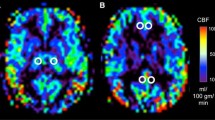

Power spectral analyses of EEG potentials recorded from scalp electrodes were used to classify corticothalamic integrity [36]. The categories were based on presence of activity in delta (< 4 Hz), theta (5–7 Hz), alpha (8–12 Hz) and beta (15–40 Hz) frequencies [14]. On one end of the spectrum, category A implies complete loss of thalamocortical circuit functional integrity, B relates to severe loss with spontaneous cortical oscillations and no thalamic output, and C relates to local cortical disinhibition with thalamic burst firing, whereas on the other end of the spectrum, category D illustrates normal activity pattern with preserved circuit functional integrity [14, 15] (Fig. 1). Accordingly, category A consists of sole delta-range activity, category B consists of predominant delta- and theta-range activity, category C consists of predominant theta and beta frequencies, and category D consists of predominant alpha and beta frequencies [15]. Background EEG pattern was also examined to confirm concordance with ‘ABCD’ spectral categorization.

An investigator blinded to all clinical details analyzed and classified all EEG segments into ‘ABCD’ spectral categories. Only patients meeting ‘ABCD’ classification were included in the primary analysis. Types A and B were grouped together (AB) as poor corticothalamic connectivity, and types C and D were grouped together (CD) as good corticothalamic connectivity for outcomes analyses. Background EEG activity was examined to ensure there was consistency between clipped segments and ongoing EEG activity.